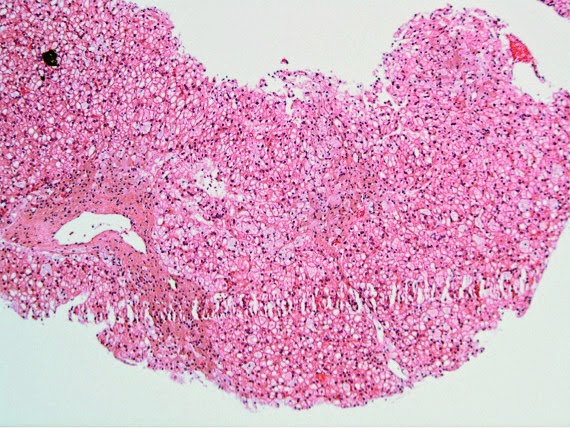

The patient was referred to a liver transplantation center and the biopsy was re-evaluated. Images from the liver biopsy are shown below.

Liver Biopsy Findings

The biopsy shows clusters of “sea-blue” cells that contain pale, foamy cytoplasmic material. These cells stain with the macrophage marker CD68, but not the hepatocyte marker Hep-Par1. The hepatocytes have mild microvesicular steatosis, but no features of steatohepatitis are apparent. Also there is only very little fibrosis. By electron micrograph, the macrophages contain laminated myelin figures.